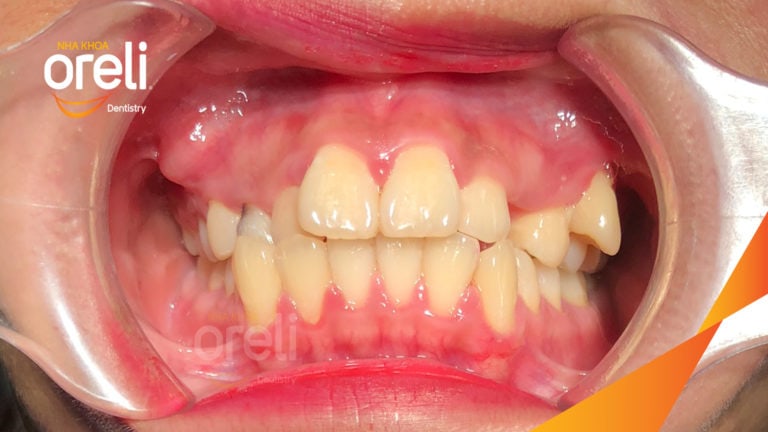

Ca niềng chỉnh chen chúc sai khớp cắn hạng 3 móm nhẹ – Kết quả thực tế ở Oreli Niềng răngChen chúcMóm Xem thêm